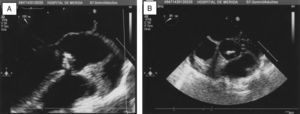

Presentamos el caso de una mujer de 36 años que consultó por artritis de tobillo izquierdo. Con antecedente de gestación con parto 5 meses antes, seguido por síndrome febril recurrente durante ese tiempo, con poliartralgias y tumefacción distal de los dedos de las manos y del tobillo izquierdo. En la exploración física se objetivó artritis en tobillo izquierdo, acropaquias en manos, soplo diastólico en foco aórtico y estertores subcrepitantes en ambas bases pulmonares. La analítica mostró anemia de enfermedades crónicas (hemoglobina: 9,8g/dl), elevación de reactantes de fase aguda (VSG: 120mm/h y PCR: 107,34mg/l), con pruebas de autoinmunidad negativas (factor reumatoide, anticuerpos antinucleares y anti péptidos cíclicos citrulinados). La ecografía músculo-esquelética confirmó la artritis del tobillo, (con señal Power-Doppler). En el ecocardiograma se observaron imágenes de vegetación sobre la válvula aórtica bicúspide parcialmente calcificada, y prolapso parcial de la misma con regurgitación severa, sin datos de insuficiencia cardiaca (fig. 1). En los hemocultivos realizados se aisló L. monocytogenes.